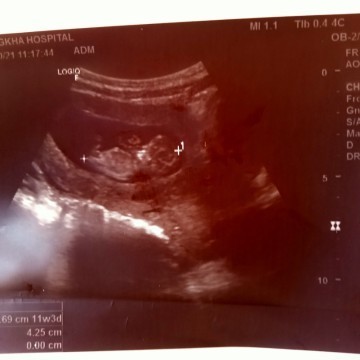

โรงพยาบาลที่นี้ตรวจให้ตอน 11wค่ะเห็นน้องครั้งแรกคือดีใจมาก